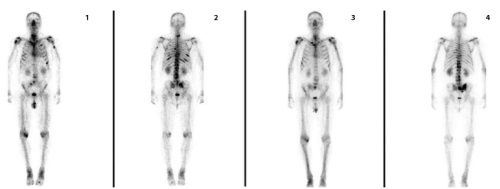

Введение. Радионуклидная терапия костных метастазов дихлоридом радия‑223 одобрена для пациентов с кастрационно-резистентным раком предстательной железы. Активно внедряемая в клиническую практику таргетная терапия позволяет улучшить показатели общей выживаемости, снизить болевые ощущения с возможностью отмены сильнодействующих анальгезирующих препаратов, уменьшить либо отсрочить риски возникновения потенциально серьезных осложнений, таких как патологические переломы и компрессия спинного мозга. Цель исследования: оценить эффективность данного препарата. Материалы и методы. С 2023 года в Клинике Башкирского государственного медицинского университета радионуклидную терапию получили 43 пациента с метастатическим кастрационно-резистентным раком предстательной железы. Перед каждым введением дихлорида радия‑223 проводился мониторинг показателей крови и простатического специфического антигена, оценка функционального статуса и болевого синдрома. Пациенты были разделены на группы в зависимости от применения дихлорида радия‑223 в качестве второй, третьей либо четвертой линии терапии. Эффективность препарата оценивалась с помощью контрольной остеосцинтиграфии. Результаты и обсуждение. У 62,7% пациентов, завершивших курс радионуклидной терапии, отмечена стабилизация процесса, что согласуется с данными ключевых публикаций крупнейшего мирового регистра. Общая выживаемость была выше в группе, получавшей терапию в качестве второй линии, по сравнению с группами из более поздних линий. В процессе лечения у 58% пациентов снизился болевой синдром, а в общей группе уровень щелочной фосфатазы снизился на 16,4%, что согласуется с данными рандомизированного исследования III фазы ALSYMPCA. Заключение. Данное исследование вносит вклад в накопление доказательной базы по оптимизации применения дихлорида радия‑223 в рутинной онкологической практике, демонстрируя клиническую эффективность препарата. Поскольку дихлорид радия‑223 противопоказан при висцеральных метастазах и рекомендован в качестве второй линии терапии, важна преемственность в работе специалистов и своевременная маршрутизация пациентов для раннего назначения.